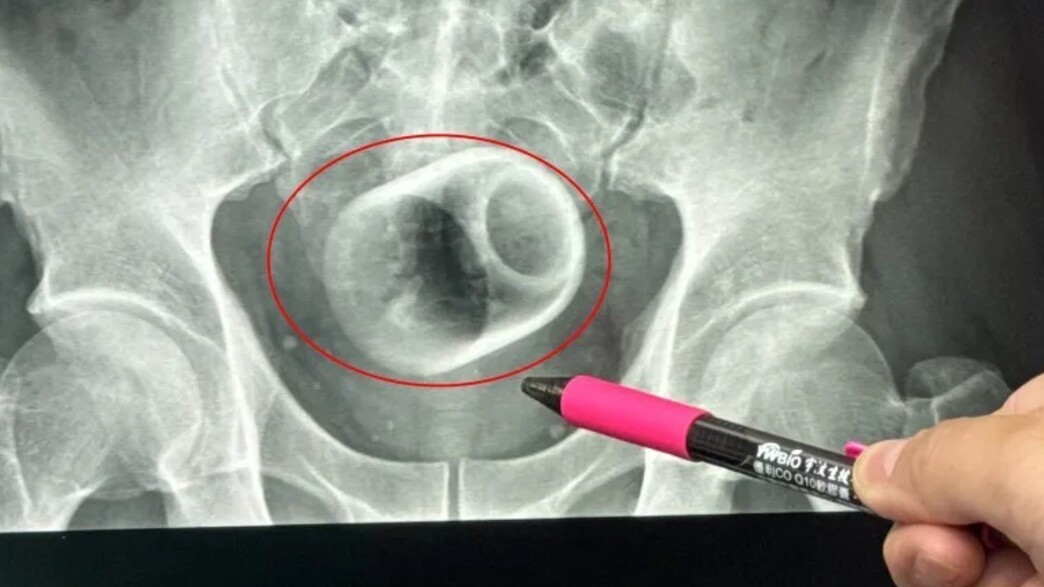

גבר הגיע לבית החולים והתלונן על עצירות, לאחר שלא הצליח ללכת לשירותים במשך שלושה ימים. הוא פנה לרופאים בבית החולים בעיר טאיצ'ונג, טייוואן, כשהוא סובל מנפיחות חמורה בבטן ומכאבים, וצילום הרנטגן חשף: בתוכו יש ספל קרמי.

הרופאים ניסו להוציא את כלי החרס, שגודלו כ-6 ס"מ על 8 ס"מ. כל הניסיונות כשלו, מאחר שהרופאים חששו ששימוש בכוח רב מדי עלול לשבור את הספל - מה שהיה גורם לפגיעה נוספת ואף לזיהום.

ההליך, שנמשך כשעתיים, אפשר לצוות הרופאים לפתוח בהצלחה את חלל הבטן והמעי של המטופל, ולהוציא את הספל. הרופא האחראי ציין שהגבר היה נבוך מכדי לספר מה באמת גרם לכאבי הבטן שלו. "באמת בלתי יאומן, אפילו אני הופתעתי כשהרנטגן נחשף", סיפר הרופא.